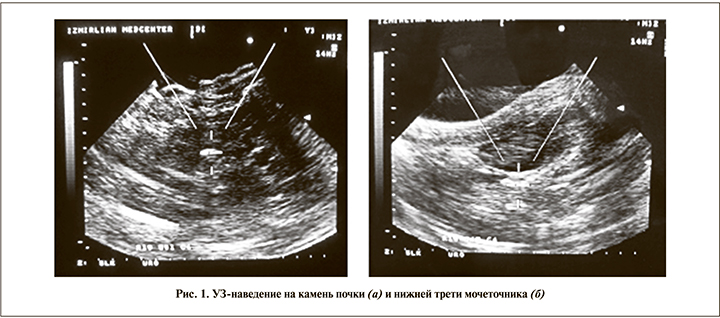

Для визуализации и локализации камней во время сеанса литотрипсии использовали только сонографию, что минимизировало лучевую нагрузку на пациента и позволяло в режиме реального времени следить за процессом. Процедуру ЭУВЛ выполняли на аппарате Modulith SLK («Storz Medical AG») с электромагнитным генератором ударных волн, в котором установлены специальный ультразвуковой датчик с частотой 3,5 MГц аппарата Aloka SSD-1400, и программа наведения StorM-Link – система сопряжения УЗИ и литотриптора, генерировавшая прицельное перекрестье, а также позволявшая улучшать качество изображения за счет смены глубины сканирования или увеличения картинки (рис. 1). Данное оборудование требует специального обучения методике и навыкам ультразвуковой визуализации камней мочевой системы, особенно – их локализации в различных отделах мочеточника для наведения источника ударных волн. Контрольные исследования для оценки результатов литотрипсии проводили через 7, 14, 30 и 90 дней после сеанса ЭУВЛ.